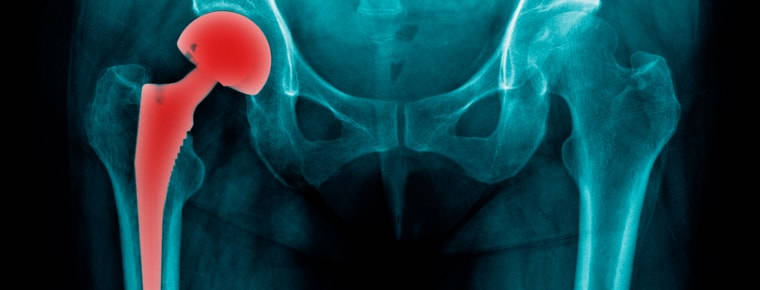

The faulty DePuy hip (DePuy ASR Hip Resurfacing System and the DePuy ASR XL Total Hip Replacement System) was recalled in Ireland in 2010 – over 1,000 people sued as a result.

But as Órla points out, the hip should never have been brought to market as it was untested on the elderly, and untested for the full range of movement and untestd in its final form.

“The hip was recalled in Australia in 2009 and they were still being inserted into patients here until August 2010. It’s truly a scandal.